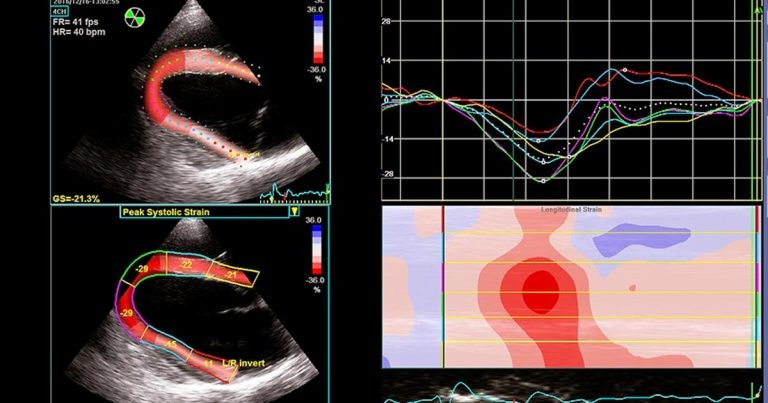

Figure 5. Speckle tracking echocardiography – in a longitudinal image of the left ventricle, offline analysis allows myocardial deformation (strain) to be documented in various regions. This is depicted as traces of longitudinal strain against time (upper right panel) and as colour-coded two-dimensional (left panels) and M-mode maps (lower right panel).

Similarly, it is fairly unusual to detect marked echocardiographic abnormalities in horses presenting with exercise-associated dysrhythmias. However, beware in those cases where the echo exam is abnormal since this may indicate important structural cardiac disease or more generalised cardiac dysfunction (Figures 4 and 5).

Two-dimensional speckle tracking allows quantification of ventricular wall motion, and evaluation of global and regional cardiac function. Each myocardial region has a unique pattern of speckles created by acoustic interfaces within the tissue. Identifying and tracking the movement of these speckle patterns identifies myocardial deformation. The relative deformation of a myocardial segment is described by strain and expressed as percentage change from its end-diastolic length. Depending on the image plane under assessment, speckle tracking can be used to evaluate longitudinal, circumferential and radial function. Critically, it is not angle-dependent, so it therefore offers much more potential than TDI in horses (Figure 6).